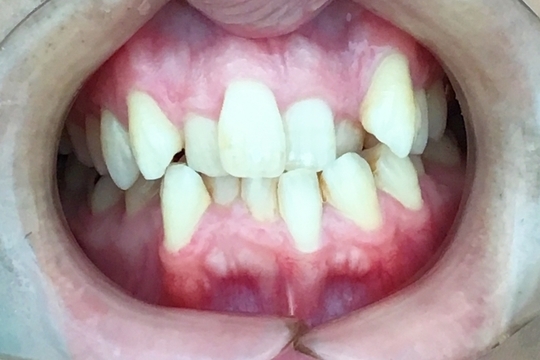

Before

浜松市中央区・自動車学校前駅のインビザラインの症例

K.M 20代女性

上の前歯が前方に出ていて横顔が気になるとの主訴でご来院。上下犬歯から犬歯までの6本が噛み合うよう、全体的に歯を内側に移動させることで、前歯の噛み合わせを整え叢生と開咬を治療しました。

​治療の期間:R5. 7/5〜R7. 1/17

​治療の価格:66万円